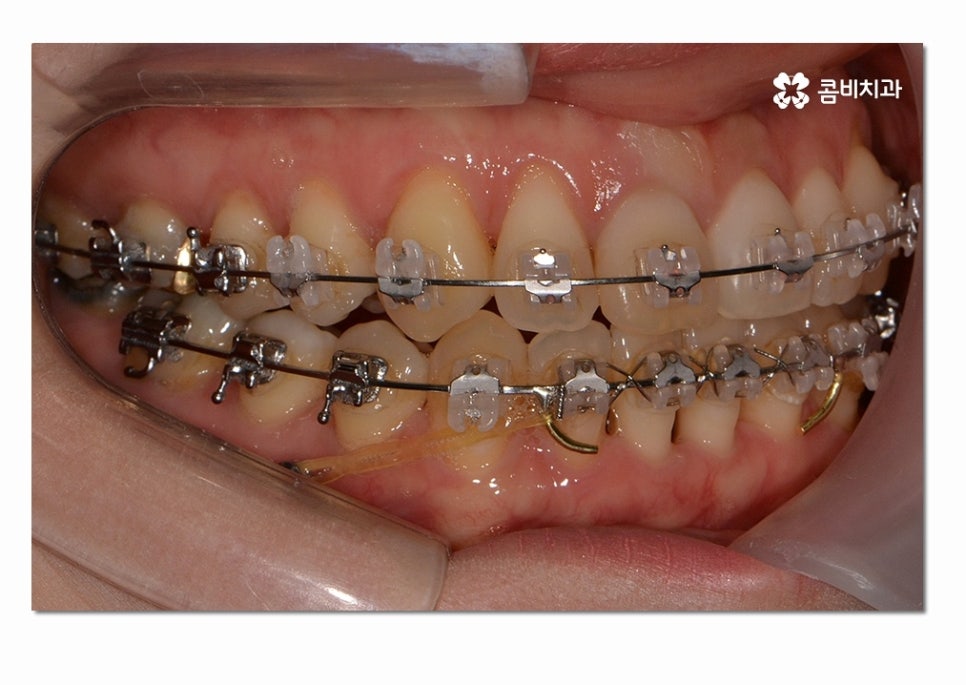

위 사례의 경우에는 3급 부정교합의 케이스로

치열이 맞지 않아 치아의 본래 기능들이 제대로 이루어지지 않고 있는 상태이며

서로 닿지 않아서 식사를 할 때마다 제대로 씹지 못하여

불편함을 느끼는 것은 물론이며 구강관리도 잘되지 않아서

충치가 많이 발생하고 있는 사례였다고 볼 수 있어요.

위 환자분의 경우에는 클리피씨 교정 장치를 통해서 치료가 진행되었으며

발치와 수술 없이 3급 부정교합을 개선한 사례라고 할 수 있어요.

치료에 사용된 클리피씨 장치의 경우 치료 기간을 단축시키고

초기 통증을 감소시킨다는 점과 심미성도 우수한 편이라는 장점이 있는데요.